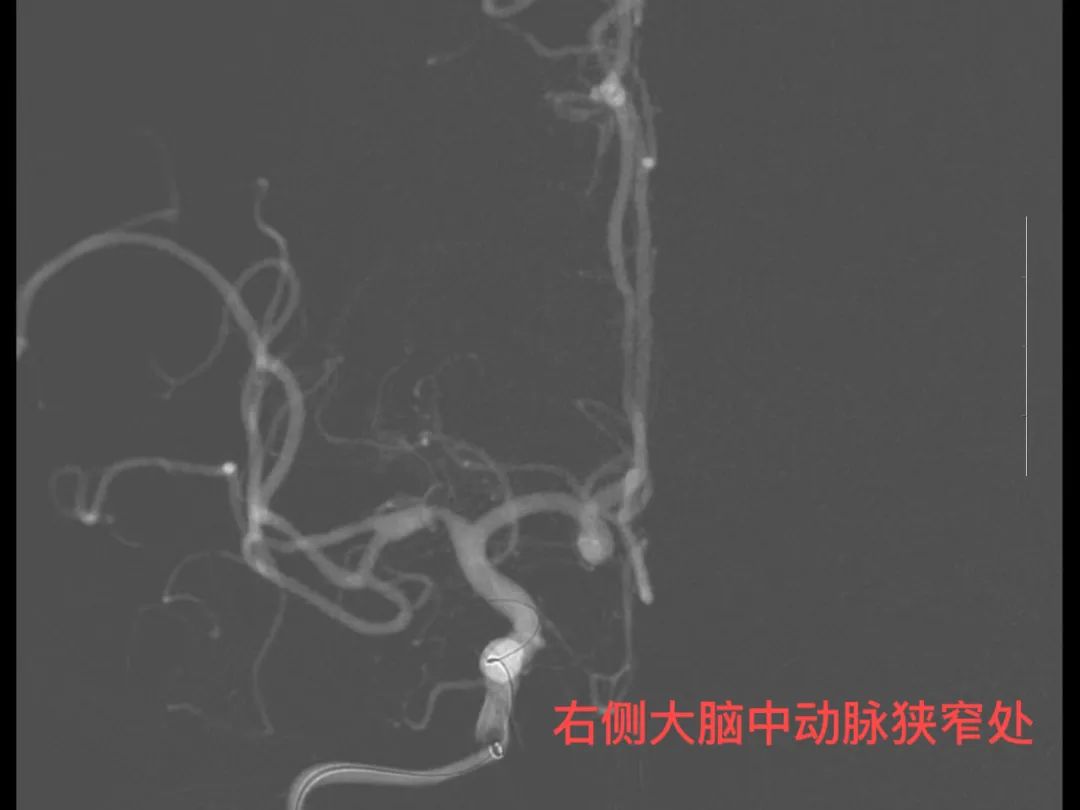

患者黄大爷,今年58岁,因头晕10小时,加重伴呕吐3小时入院,既往“高血压、脑梗死、冠心病”病史,入院后查磁共振示桥脑及右侧颞叶急性脑梗死、脑内多动脉狭窄,情况危急。

针对患者病情,神经内科团队决定行脑血管造影进一步查看。在征得患者及家属同意、排除手术禁忌症、病情稳定后即开始脑血管造影。术中发现右侧大脑中动脉M1段重度狭窄,告知患者及家属大动脉狭窄的危险性,患者及家属同意后全麻行右侧大脑中动脉球囊扩张成形术,手术顺利,患者生命体征平稳,术后患者穿刺口恢复良好,告知患者术后相关注意事项,观察两天后现患者已病情稳定出院。此次治疗,患者血管开通良好,是我院神经内科团队的又一次进步,成功减少了脑梗死复发几率,为患者后续生活质量提供了保障。